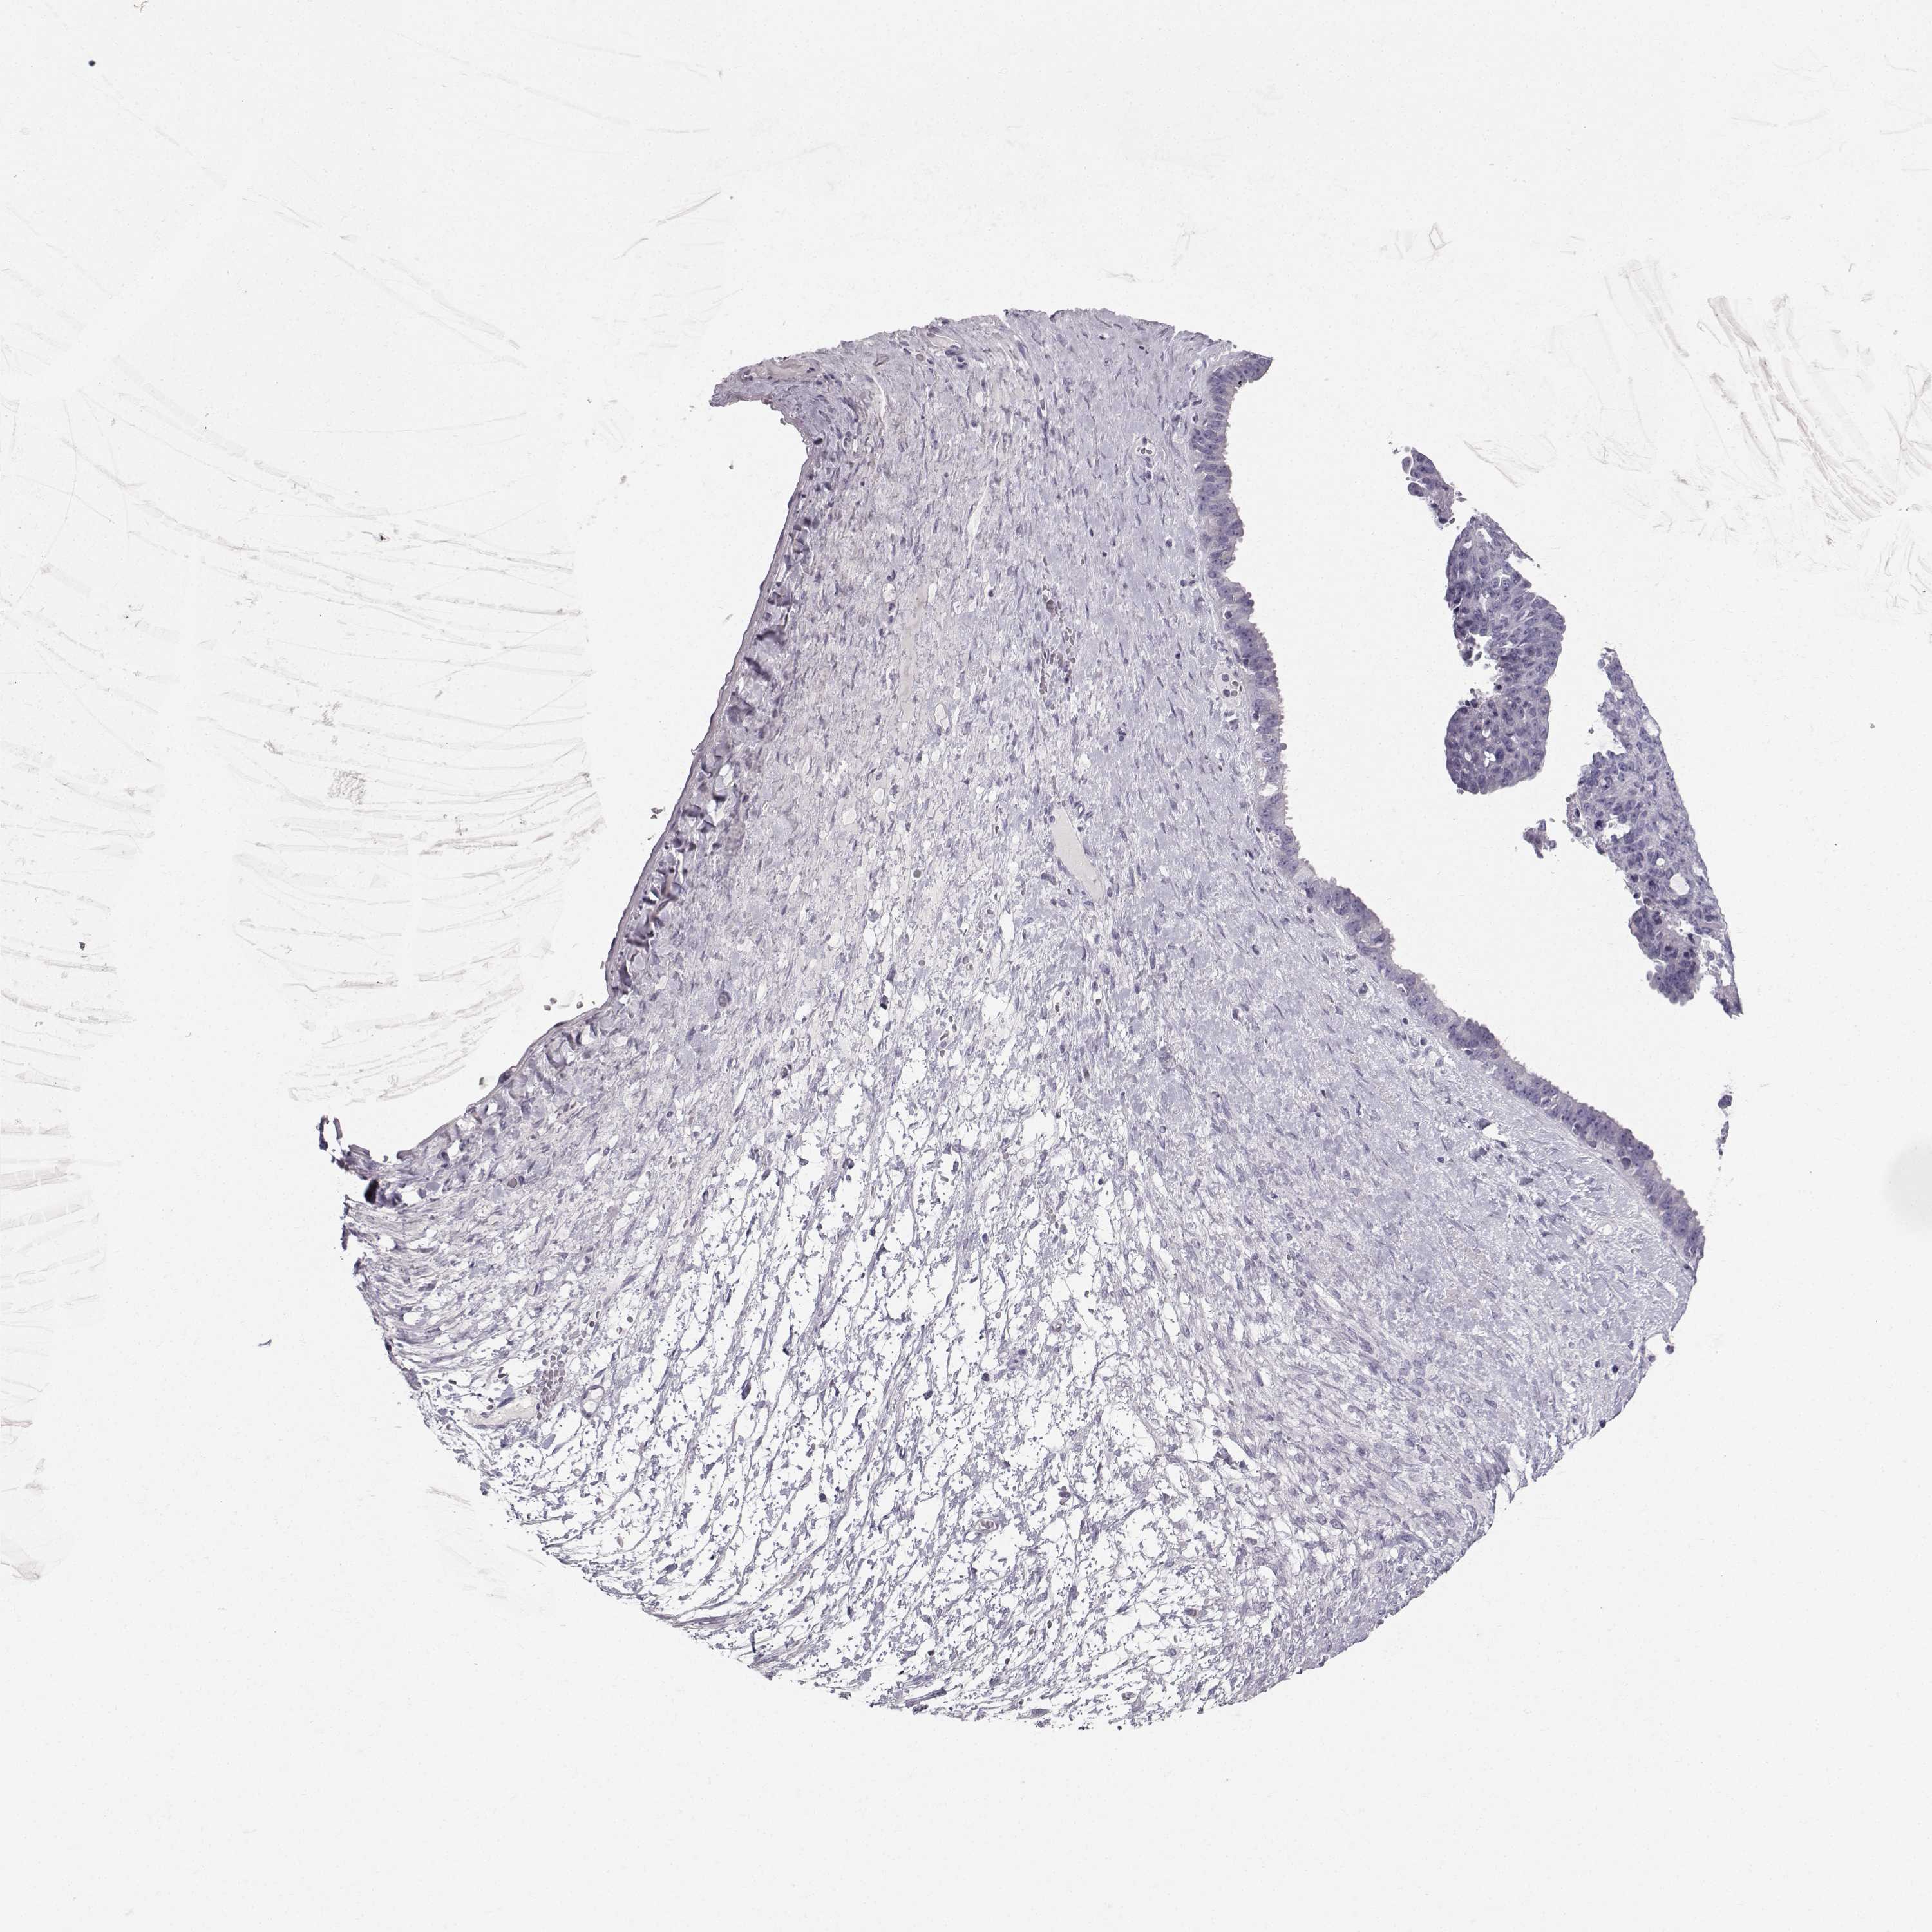

OVARIAN CANCER - Protein expressioni

A mouse-over function shows sample information and annotation data. Click on an image to view it in a full screen mode. Samples can be filtered based on level of antibody staining by selecting one or several of the following categories: high, medium, low and not detected. The assay and annotation is described here.

Note that samples used for immunohistochemistry by the Human Protein Atlas do not correspond to samples in the TCGA dataset.

Antibody stainingi

Antibody staining in the annotated cell types in the current human tissue is reported as not detected, low, medium, or high, based on conventional immunohistochemistry profiling in selected tissues. This score is based on the combination of the staining intensity and fraction of stained cells.

Each image is clickable and will lead to virtual microscopy that enables deeper exploration of all samples and also displays staining intensity scores, fraction scores and subcellular localization as well as patient and tissue information for each sample.

Antibody HPA055162

Staining

High

Medium

Low

Not detected

Intensity

Strong

Moderate

Weak

Negative

Quantity

>75%

75%-25%

<25%

None

Location

Nuclear

Cytoplasmic/membranous

Cytoplasmic/membranous,nuclear

Cystadenocarcinoma, serous, NOS

Cystadenocarcinoma, mucinous, NOS

Carcinoma, endometroid